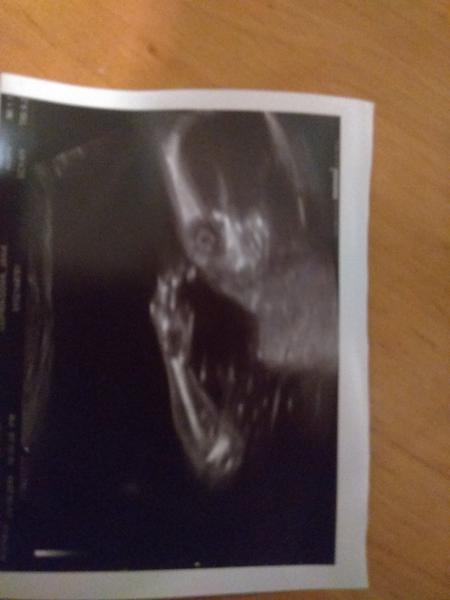

@spokojena_maminka Na chlapecka jo- to víme od zacatku. Chceme Alféreda 🙂. Na holcicku nevíme, ale asi nebude ani potřeba 😊. My jsme chtěli klidne i 3 deti, ale zase jestli to bude chlapeček, tak nevim, jestli riskovat třetího 😅. Ne, ze by byl první syn nějaký náročný, ale taková tlupa 3 kluků uz asi dá zabrat 😅...Jinak dr.na screeningu si byl celkem jistý... jsem potom řešil, ze nevidí ruku. Ze ji má schovanou pod zadkem, tak jsme vtipkovali, jestli ten pindik nebyl třeba palec 🙈, ale uz to bylo po UZ, takže jsme v tom nestourali. Ale vidím to tak, ze holka je to tak na 5% maximálně...

@kris5 to jo ,ty jo a kuličky si tam n viděla? To je základ , pinďu si spletes i s pupucnikem ale kuličky jsou základ.U nás bylo krásně vše vidět ,jako když nakreslis obrázek 😂